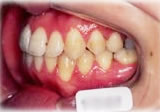

開咬症例

初診時年齢○○歳。前歯部での咬合不全を主訴に来院。

骨格性開咬と診断し、外科的処置を併用して治療。

矯正治療は上下顎歯列を拡大しスペースを作成、非抜歯にて行った。

右側面 右側面 右側面

左側面 左側面 左側面